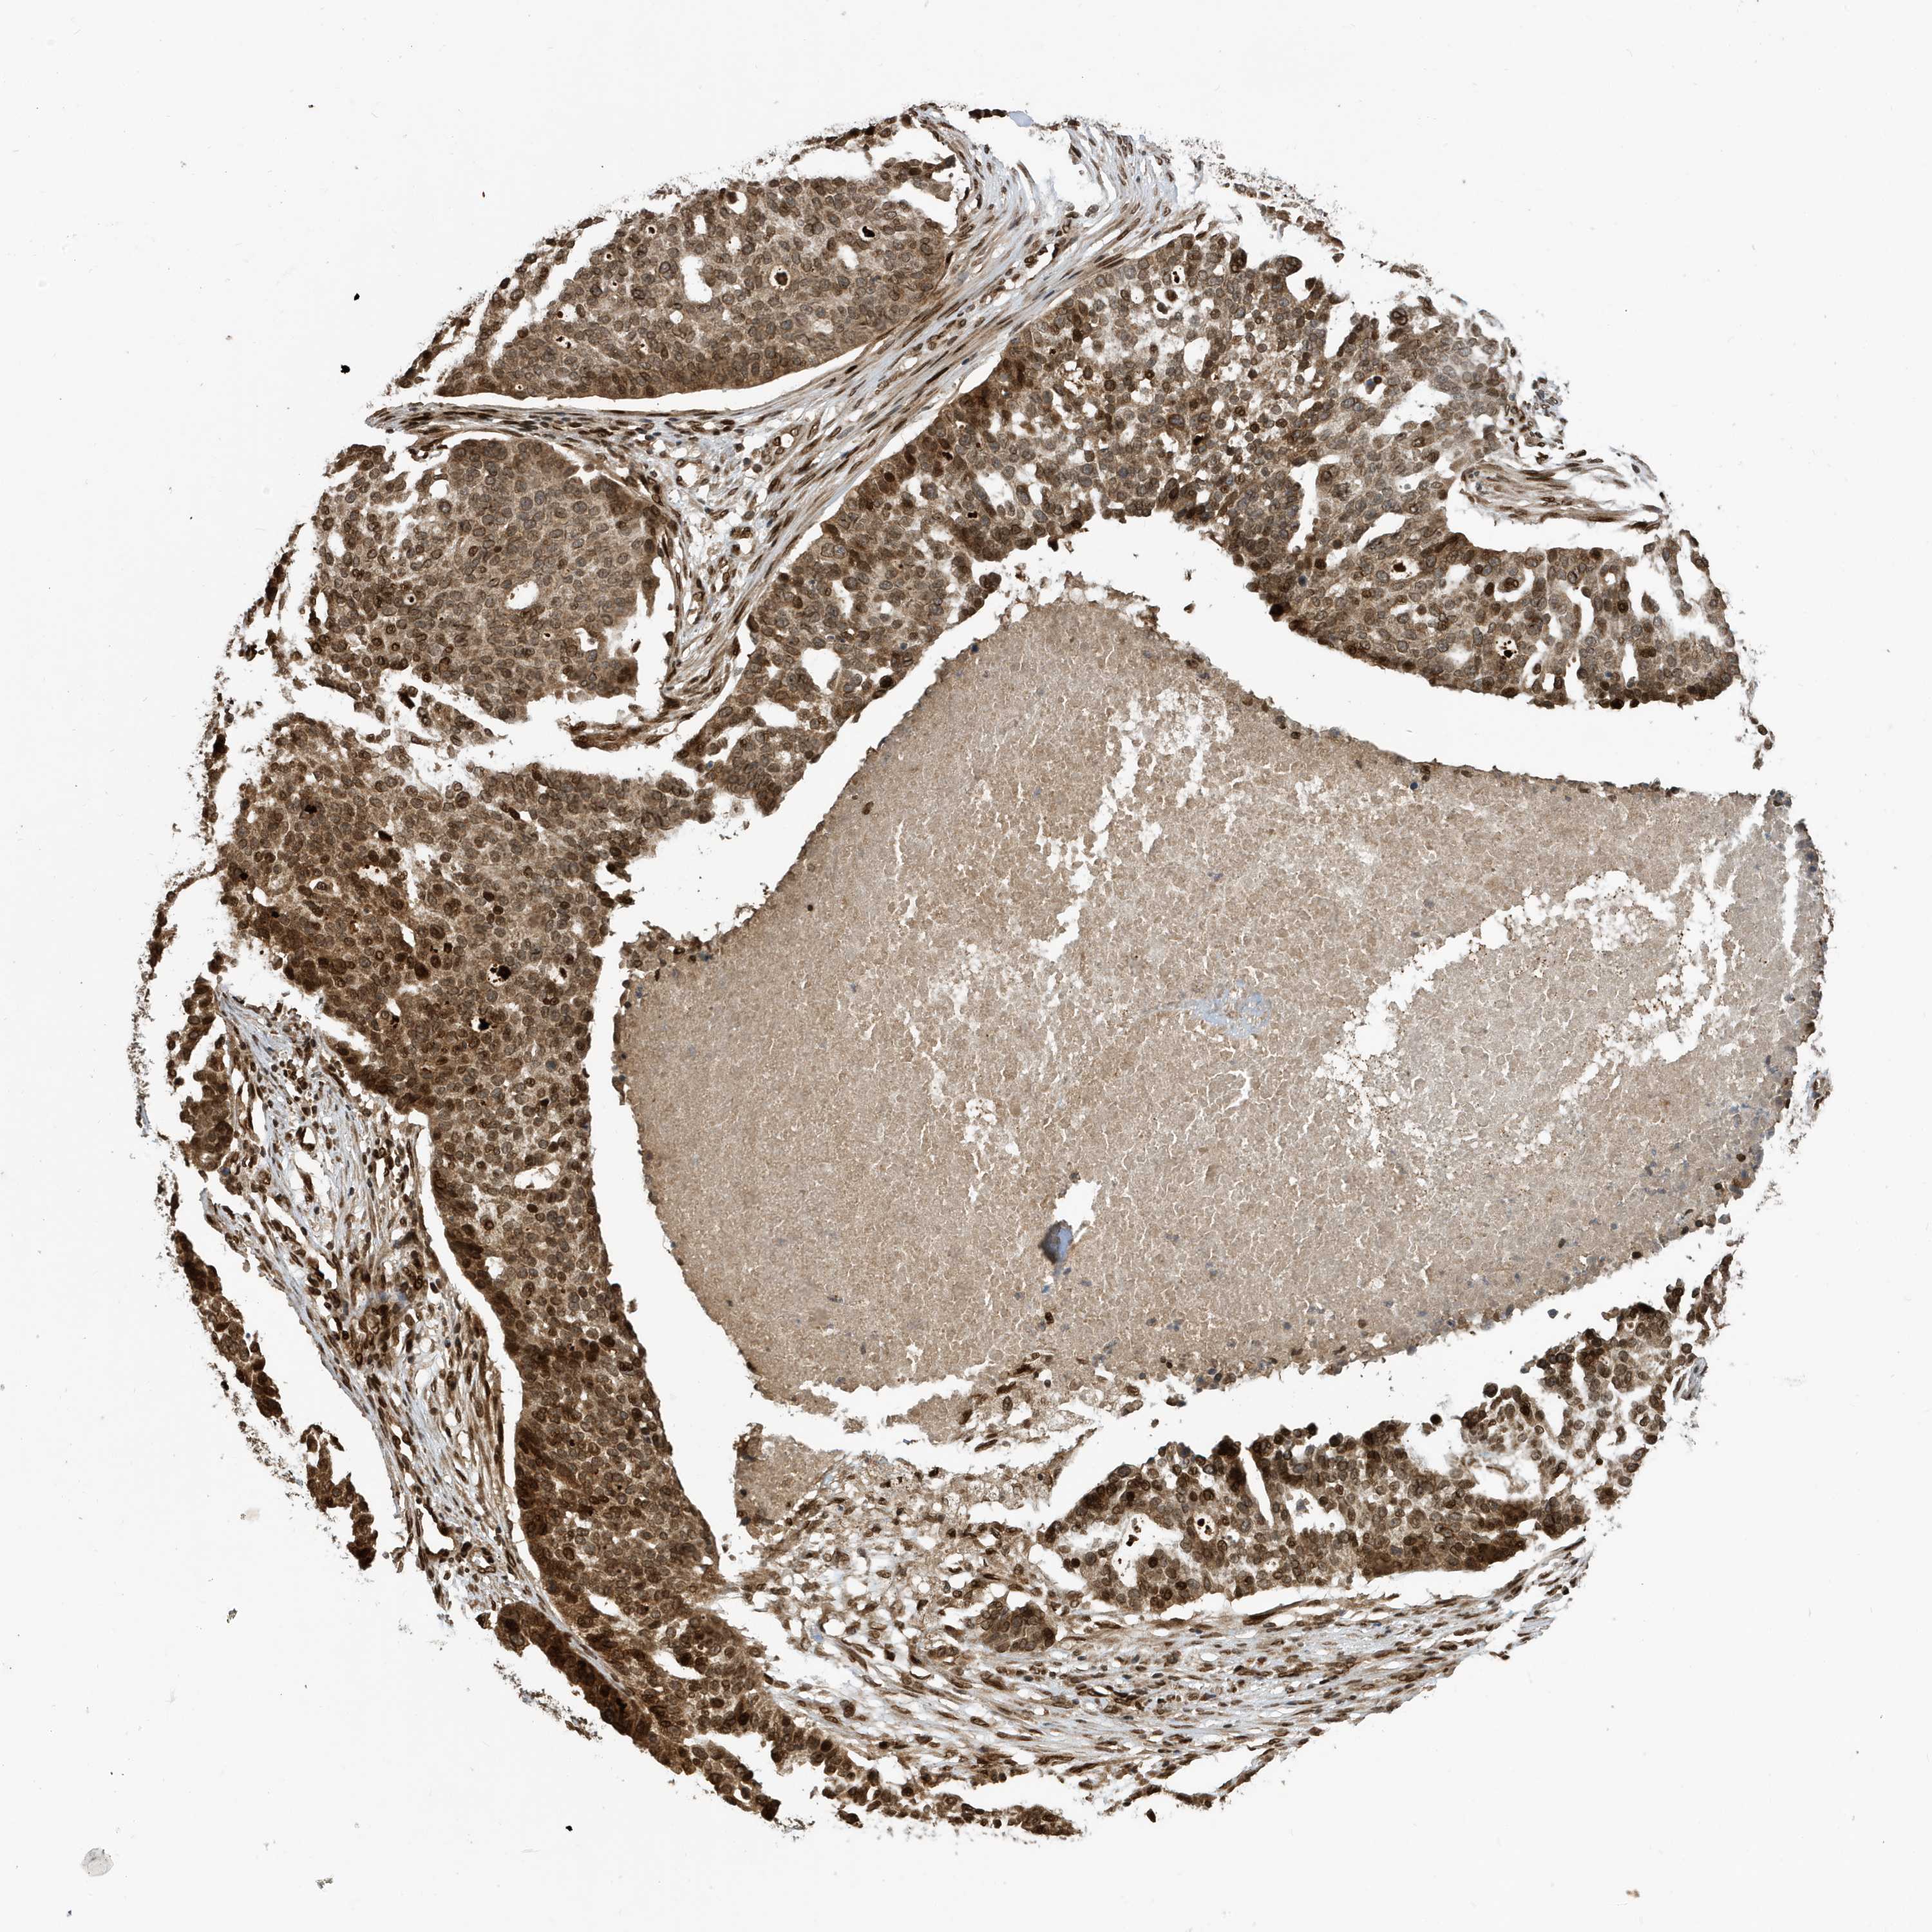

OVARIAN CANCER - Protein expressioni

A mouse-over function shows sample information and annotation data. Click on an image to view it in a full screen mode. Samples can be filtered based on level of antibody staining by selecting one or several of the following categories: high, medium, low and not detected. The assay and annotation is described here.

Note that samples used for immunohistochemistry by the Human Protein Atlas do not correspond to samples in the TCGA dataset.

Antibody stainingi

Antibody staining in the annotated cell types in the current human tissue is reported as not detected, low, medium, or high, based on conventional immunohistochemistry profiling in selected tissues. This score is based on the combination of the staining intensity and fraction of stained cells.

Each image is clickable and will lead to virtual microscopy that enables deeper exploration of all samples and also displays staining intensity scores, fraction scores and subcellular localization as well as patient and tissue information for each sample.

Antibody CAB034070

Staining

High

Medium

Low

Not detected

Intensity

Strong

Moderate

Weak

Negative

Quantity

>75%

75%-25%

<25%

None

Location

Nuclear

Cytoplasmic/membranous

Cytoplasmic/membranous,nuclear

Cystadenocarcinoma, serous, NOS

Carcinoma, endometroid

Cystadenocarcinoma, mucinous, NOS

Carcinoma, NOS